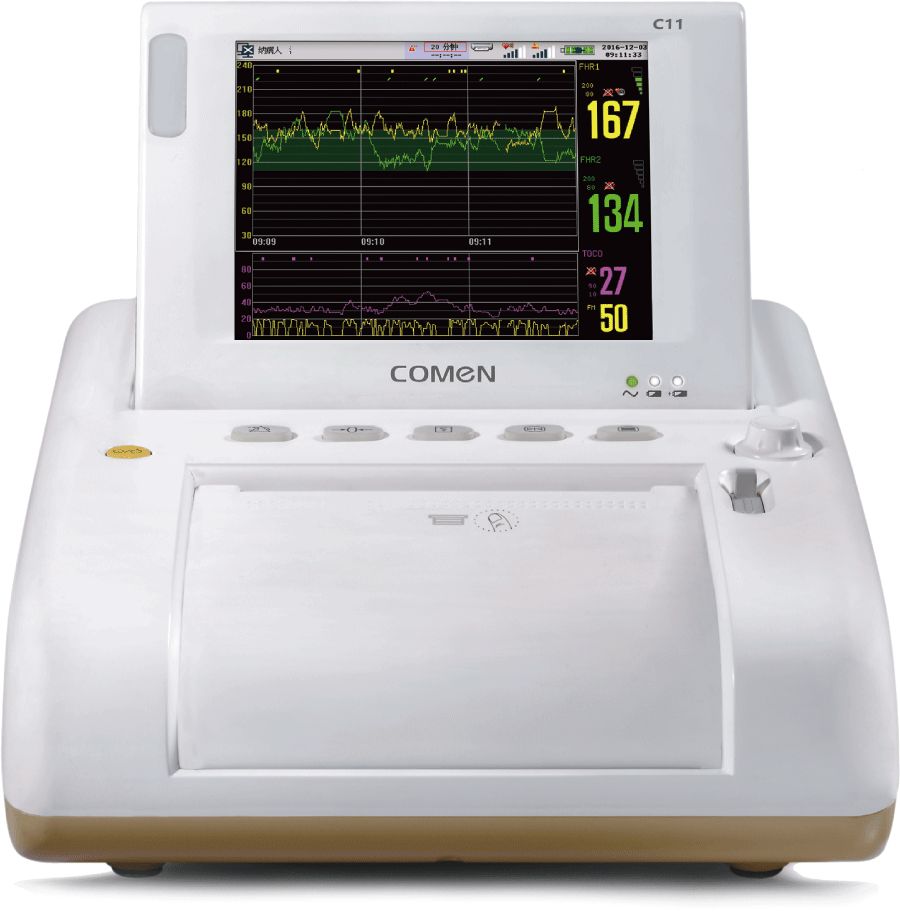

Comen C11 Specialized Fetal Monitor